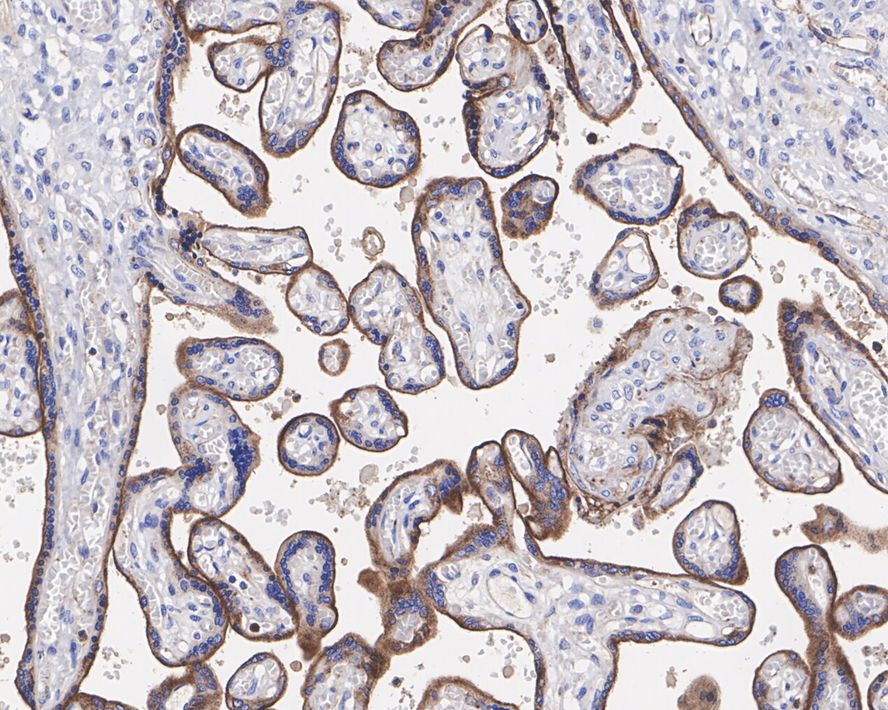

Immunohistochemical analysis of paraffin-embedded human placenta tissue with Rabbit anti-VISTA antibody (HA750641) at 1/1,000 dilution.

The section was pre-treated using heat mediated antigen retrieval with Tris-EDTA buffer (pH 9.0) for 20 minutes. The tissues were blocked in 1% BSA for 20 minutes at room temperature, washed with ddH2O and PBS, and then probed with the primary antibody (HA750641) at 1/1,000 dilution for 1 hour at room temperature. The detection was performed using an HRP conjugated compact polymer system. DAB was used as the chromogen. Tissues were counterstained with hematoxylin and mounted with DPX.